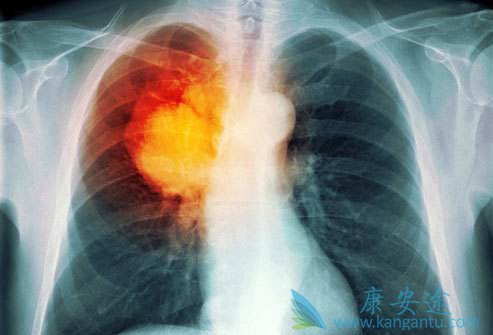

肺癌发展到了肺癌晚期有什么症状

由于空气污染、吸烟等因素,肺癌的发病率逐年递增,且在世界范围内,肺癌为最危险的恶性肿瘤之一,其被称为癌中之癌王。据报道,绝大多数患者被确诊为肺癌时均以到了癌症中晚期,那么,肺癌晚期有什么症状

肺癌晚期有什么症状

发生区域性扩散的肺癌晚期患者几乎都有不同程度的气促。由肺和心肌产生的正常组织液由胸正中的淋巴结回液。若这些淋巴结被肿瘤阻塞,这些组织液将积聚在心包内形成心包积液或积聚在胸腔内形成胸腔积液。以上两种情况均可导致气促。控制左侧发音功能的喉返神经由颈部下行至胸部,绕过心脏的大血管返行向上至喉,从而支配发音器官的左侧。因此,若肿瘤侵及纵隔左侧,使喉返神经受到压迫,声嘶便产生了,但却无咽痛及上呼吸道感染的其它症状。

出现疼痛往往提示癌症已进入中、晚期。开始多为隐痛或钝痛,夜间明显。以后逐渐加重,变得难以忍受,昼夜不停,剧烈疼痛是肺癌晚期临终前症状,若是出现一般通过药物进行控制。疼痛一般是癌细胞侵犯神经造成的。很多人晚期都会感到无比疼痛,甚至吃药都不管用。由于某些体表癌的癌组织生长快,营养供应不足,出现组织坏死所形成的。如某些乳腺癌可在乳房处出现火山口样或菜花样溃疡,分泌血性分泌物,并发感染时可有恶臭味。此外,胃、结肠癌也可形成溃疡,一般只有通过胃镜、结肠镜才可观察到。